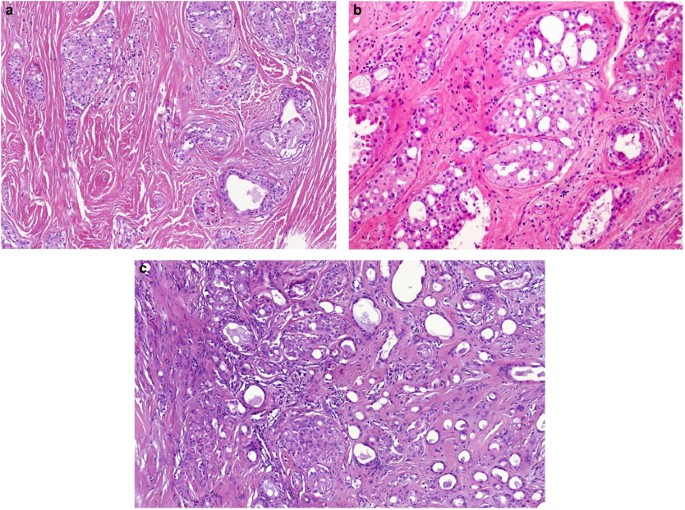

Grossly, the tumors are unencapsulated, white to gray in color, and hard in consistency, usually with no areas of necroses and hemorrhages, covered by nonulcerated intact epithelium (Figure 8a).

Cribriform adenocarcinoma of minor salivary glands (CAMSGs). CAMSG is composed predominantly of cribriform, solid and glomeruloid structures. The tumor is covered by intact mucosal epithelium (a) and lymphovascular invasion is often observed (b). The histological structure of CAMSG is quite characteristic with cribriform, tubular, glomeruloid or solid areas separated by fibrous tissue (c). In solid areas, the tumor nests are frequently detached from the surrounding fibrous stroma by clefts and often contains central necrosis (d). Characteristic feature seen in more than one-third of CAMSGs is presence of mucinous stroma composed of mucinous matrix and rare spindle cell myofibroblasts (e). Overlapping clear 'Orphan Annie eye-like nuclei' of CAMSG are remarkably similar to those of papillary thyroid carcinoma (f).

Histologically, the tumors have invasive margins and in most cases they infiltrate the muscular layer of the tongue and/or adjacent tissues. Lymphovascular invasion is observed in a third of cases (Figure 8b). The tumors are composed predominantly of cribriform (Figure 8c) to microcribriform and solid structures (Figure 8d) in variable proportions. Rare tumors may have an overtly cystic configuration. In most instances, the tumor architecture consists mainly of a solid mass divided by fibrous septa into irregularly shaped and sized nodules composed of centrally necrotic areas. In the solid areas, the tumor nests are frequently detached from the surrounding fibrous stroma by clefts (Figure 8d). The peripheral layer of such solid tumor nests often displays hyperchromatic nuclei in a somewhat palisaded pattern. In rare cases, psammoma bodies are found. Another characteristic feature seen in most cases is presence of mucinous spindle cell myofibroblastic stromal septa, composed of mucinous matrix and rare spindle cell myofibroblasts, seen mostly in early infiltrative foci (Figure 8e). The most prominent feature of the tumors, however, is the appearance of the nuclei. These often overlap one with another, and are pale, optically clear and vesicular with a ground glass appearance. Rarely, there are solid areas composed of these cells with optically clear nuclei. Cellular atypia is mild, and mitotic figures are in most cases rare. Generally, there are one to three small inconspicuous nucleoli. The cytoplasm is clear to eosinophilic. Cytologically, all tumors are composed of one cell type. The overall morphology of the tumor, particularly with focal papillary growth and with overlapping clear 'Orphan Annie eye-like nuclei', is remarkably similar to various variants of papillary thyroid carcinoma (Figure 8f). The cervical lymph node metastases have usually identical appearances to the primary tumors.